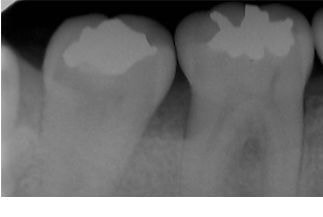

マイクロスコープによる原因歯の特定

問診・視診・打診・温度診・レントゲンなどの検査を行っても原因が特定できない場合でも、マイクロスコープで検査を行うことで何が原因になっているか特定できる症例はたくさんあります。